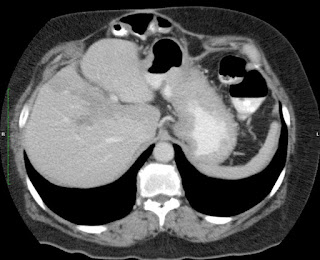

Mujer de 57 años.

Cuadro clínico de 1 mes de evolución caracterizado por distensión abdominal e hiporexia.